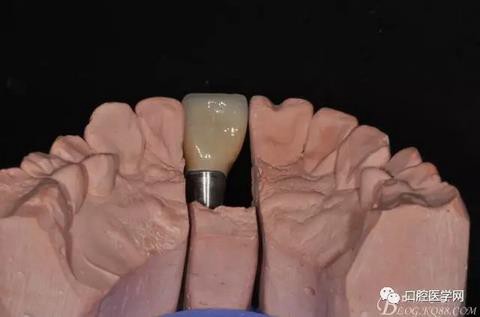

圖16 修復(fù)基臺(tái)模型頜面照

圖17 烤瓷冠唇側(cè)照

圖18 烤瓷冠舌側(cè)照